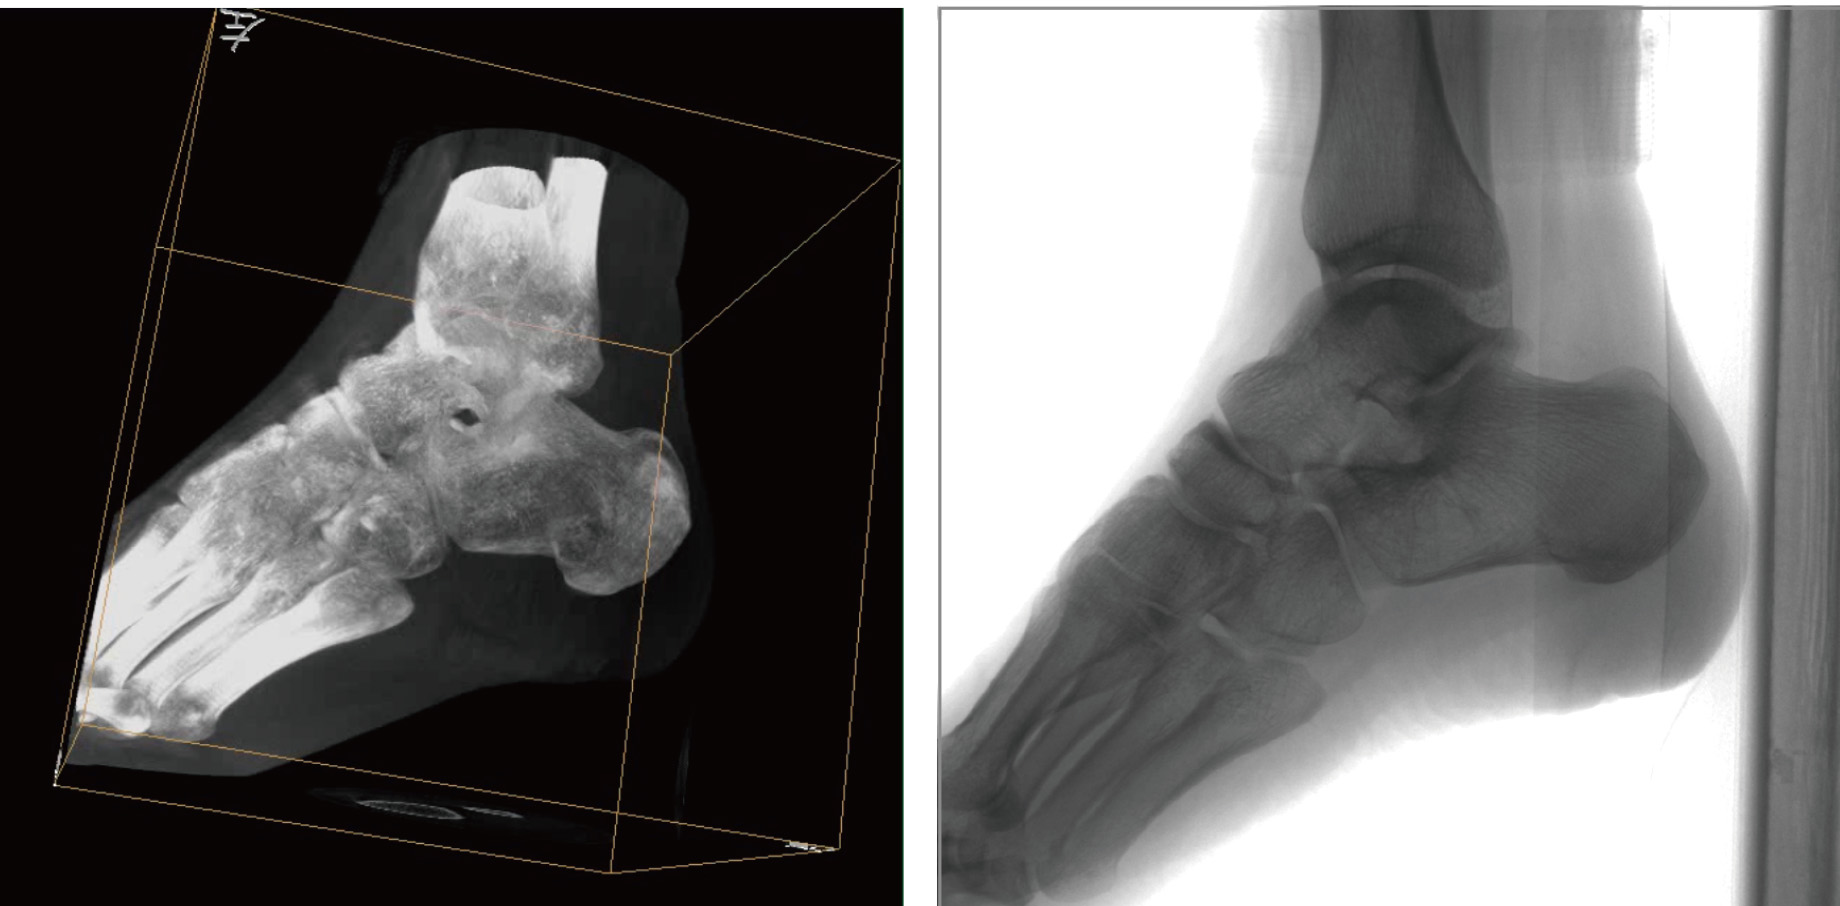

普爱医疗天弓PLX7500骨科三维C形臂,作为“术中CT”,在手术中快速生成类CT断层图像和立体三维图像,为医者提供更全面的图像信息,能够准确地观察植入物的情况,例如螺钉内固定术入钉的位置和角度。天弓PLX7500三维C形臂性能特点:

PLX7500骨科三维C形臂通过采集,能在术中快速地生成横断面、矢状面、冠状面和可旋转的立体图像,给术者提供360°无死角的观察角度,准确判断骨组织和植入物的情况,为手术的实施提供保障,极大提高手术成功率,减少并发症概率。

动态平板探测器。采用30cm x 30cm的动态平板探测器,输出高分辨率、大尺寸的二维、三维图像。较高16比特灰阶度,高动态范围清晰显示植入物的位置和轮廓。

超大区域,超高像素。术中三维成像区域可达直径Φ18cm,高18cm的圆柱形区域,各个维度均为400立体像素,画质细腻清晰。